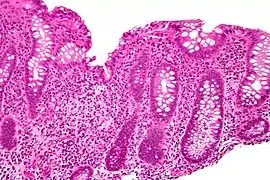

Crypt abscess. H&E stain.